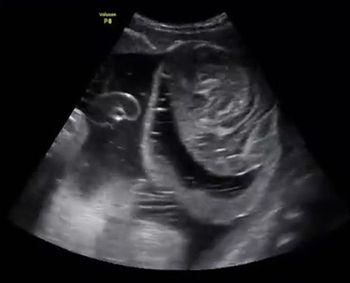

QUIZ: What is your diagnosis based on these fetal echo images?